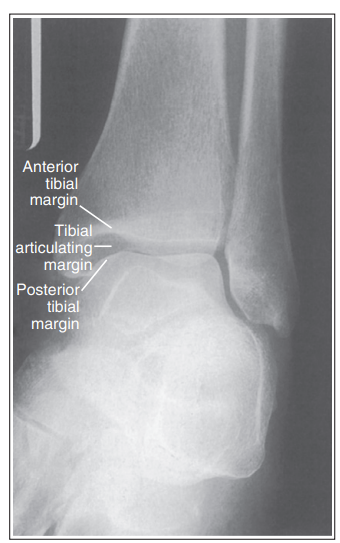

tibia superimposes more than ½ of the fibular, medial mortise is closed

Anterior tibial margin is lateral to posterior margin

External rotation

tibia superimposes less than ½ of fibula, medial mortise is closed

Posterior tibial margin is lateral to anterior and is superimposed by talus

Internal rotation